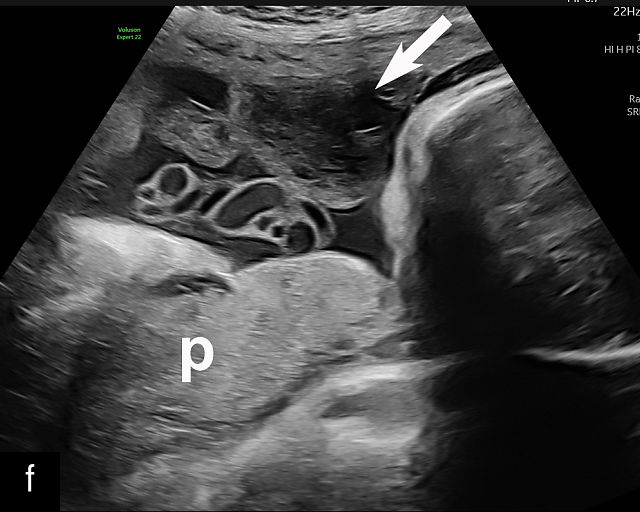

6

Placenta accreta spectrum. (a,b) Sagittal transabdominal grayscale ultrasound of the lower uterus and cervix demonstrating placenta previa accreta, with the placenta (p) containing prominent irregular hypoechoic lacunae. There is absence of the myometrium at the bladder (b) interface (arrows) c, cervix. (c) Sagittal transabdominal color Doppler ultrasound of the lower uterus and cervix demonstrating placenta previa accreta, with increased vascularity of the lower uterus and the myometrial bladder interface. (d) Transvaginal ultrasound of placenta previa accreta showing multiple lacunae involving the cervix with no clear demarcation between the placenta and the cervix. (e) Transvaginal ultrasound of placenta previa accreta showing multiple large irregular lacunae involving the cervix with no clear demarcation between the placenta (p) and the cervix. The placenta has a ‘moth-eaten’ appearance. There is loss of myometrium (arrows). (f) Transvaginal ultrasound of placenta previa accreta without and with color flow Doppler showing multiple large irregular lacunae. The placenta has a ‘moth-eaten’ appearance. There is hypervascularity of the myometrial interface. (g) Transvaginal ultrasound of placenta previa accreta showing multiple lacunae involving the cervix with no clear demarcation between the placenta and the cervix. (h) Transvaginal ultrasound of placenta previa accreta with color flow Doppler showing hypervascularity of the myometrial interface and irregularity of the bladder wall. b, bladder; p, placenta. (i) Transabdominal grayscale ultrasound of cesarean scar pregnancy. The uterine fundus (f) is empty (arrowhead). The gestational sac (arrow) is located in the lower uterus, anterior to the uterine canal, and lies above the cervix (c). b, bladder. (j) Transvaginal grayscale ultrasound image of cesarean scar pregnancy showing the empty fundus (f) and the normal cervix (c). The gestational sac lies below the fundus, above the cervix and anterior to the uterine cavity. (k) Transvaginal grayscale ultrasound image of cesarean scar pregnancy showing the empty cavity (arrowheads) of the uterine fundus (f), and the normal cervix (c). The gestational sac lies below the fundus, above the cervix and anterior to the uterine cavity (arrow).

Several characteristic sonographic findings are associated with PAS.90,95,96,97 These include placental lacunae, which appear as hypoechoic, irregular spaces within the placenta with high-velocity turbulent flow on color Doppler.16,50 Other features include obliteration of the retroplacental clear space, thinning of the myometrium in the lower uterine segment, irregularity and hypervascularity of the myometrial–bladder interface, and placental bulging into the bladder (Figure 6a–h).90,96,98,99